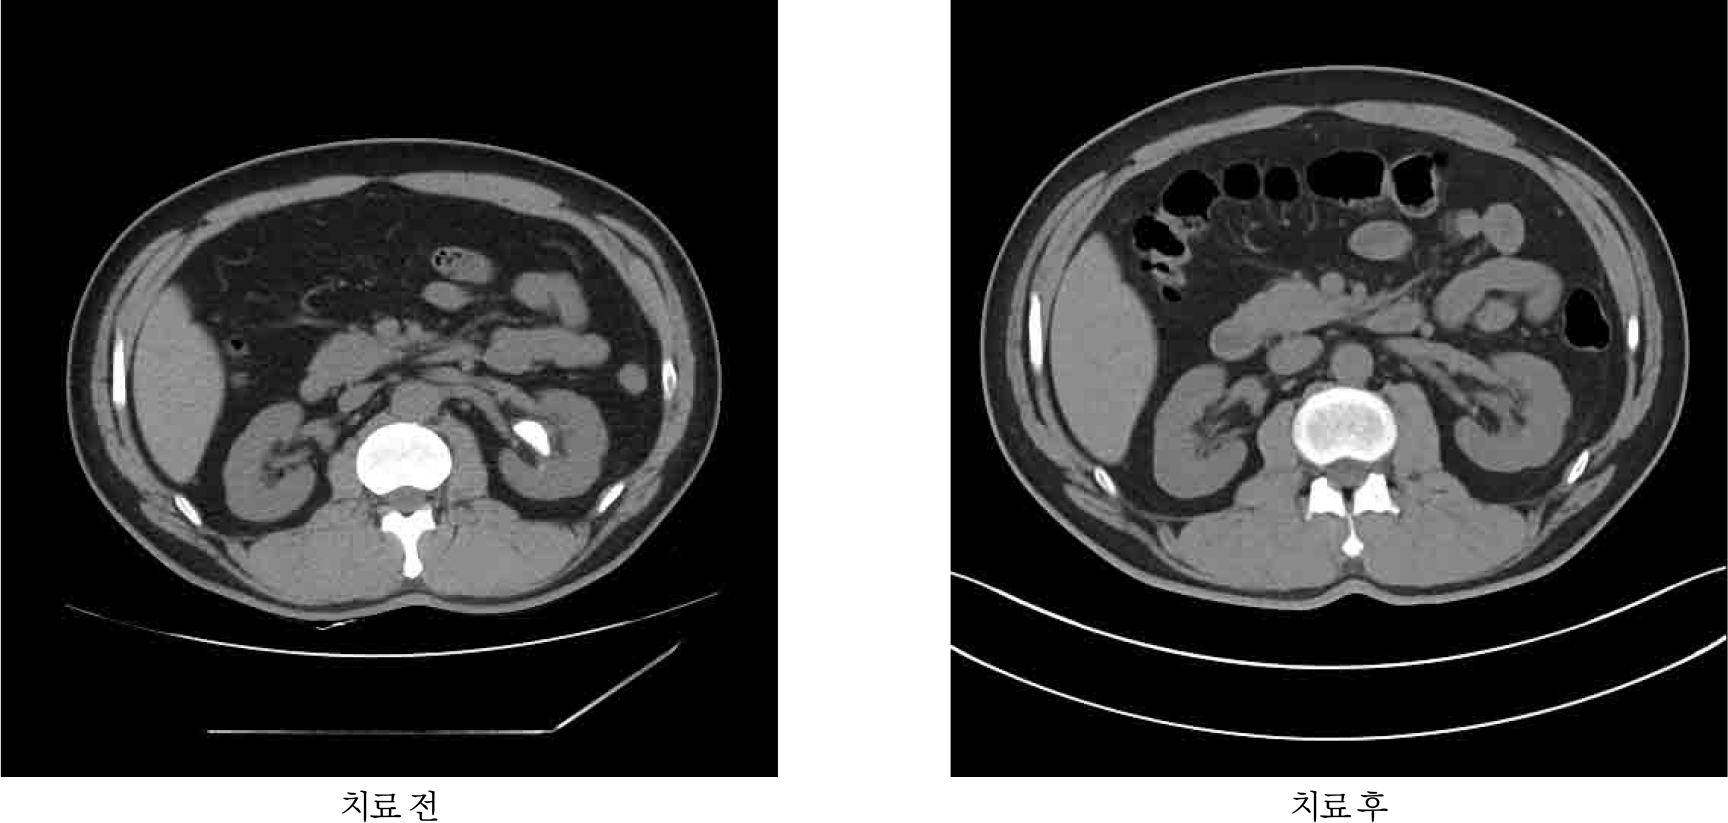

경구약물을 이용한 결석의 용해요법 [그림 1]은 주로 국내에서도 사용가능한 구연산칼륨 (potassium citrate, Urocitra®) 제제나 탄산수소나트륨 (sodium bicarbonate, Tasna®) 제제를 이용하여 시행되며, 구연산칼륨이 소변에 좀 더 높은 농도로 용해되어 우선적으로 추천되나 고칼륨혈증 등의 부작용이 발생할 수 있어, 만성신병증 등 고위험군 환자나 약물 복용 후 고칼륨혈증이 발생한 환자에서는 대안으로 탄산수소나트륨 제제가 추천된다 [4]. 경구약물을 이용한 결석 용해요법의 성공률은 지금까지 약 50-73%에 이르는 것으로 보고되었으며, 요산석으로 의심되는 낮은 요 pH (<6.0) 및 CT 상 Hounsfield units이 450 미만인 방사선투과성 결석의 경우에 시행하는 것이 추천된다 [26]. 약물복용 기간 중에는 요중 pH 및 혈중 칼륨 레벨에 대한 모니터링이 필요하며, 요 중 pH는 6.5-7.0 사이를 유지하는 것이 권고된다 [26].